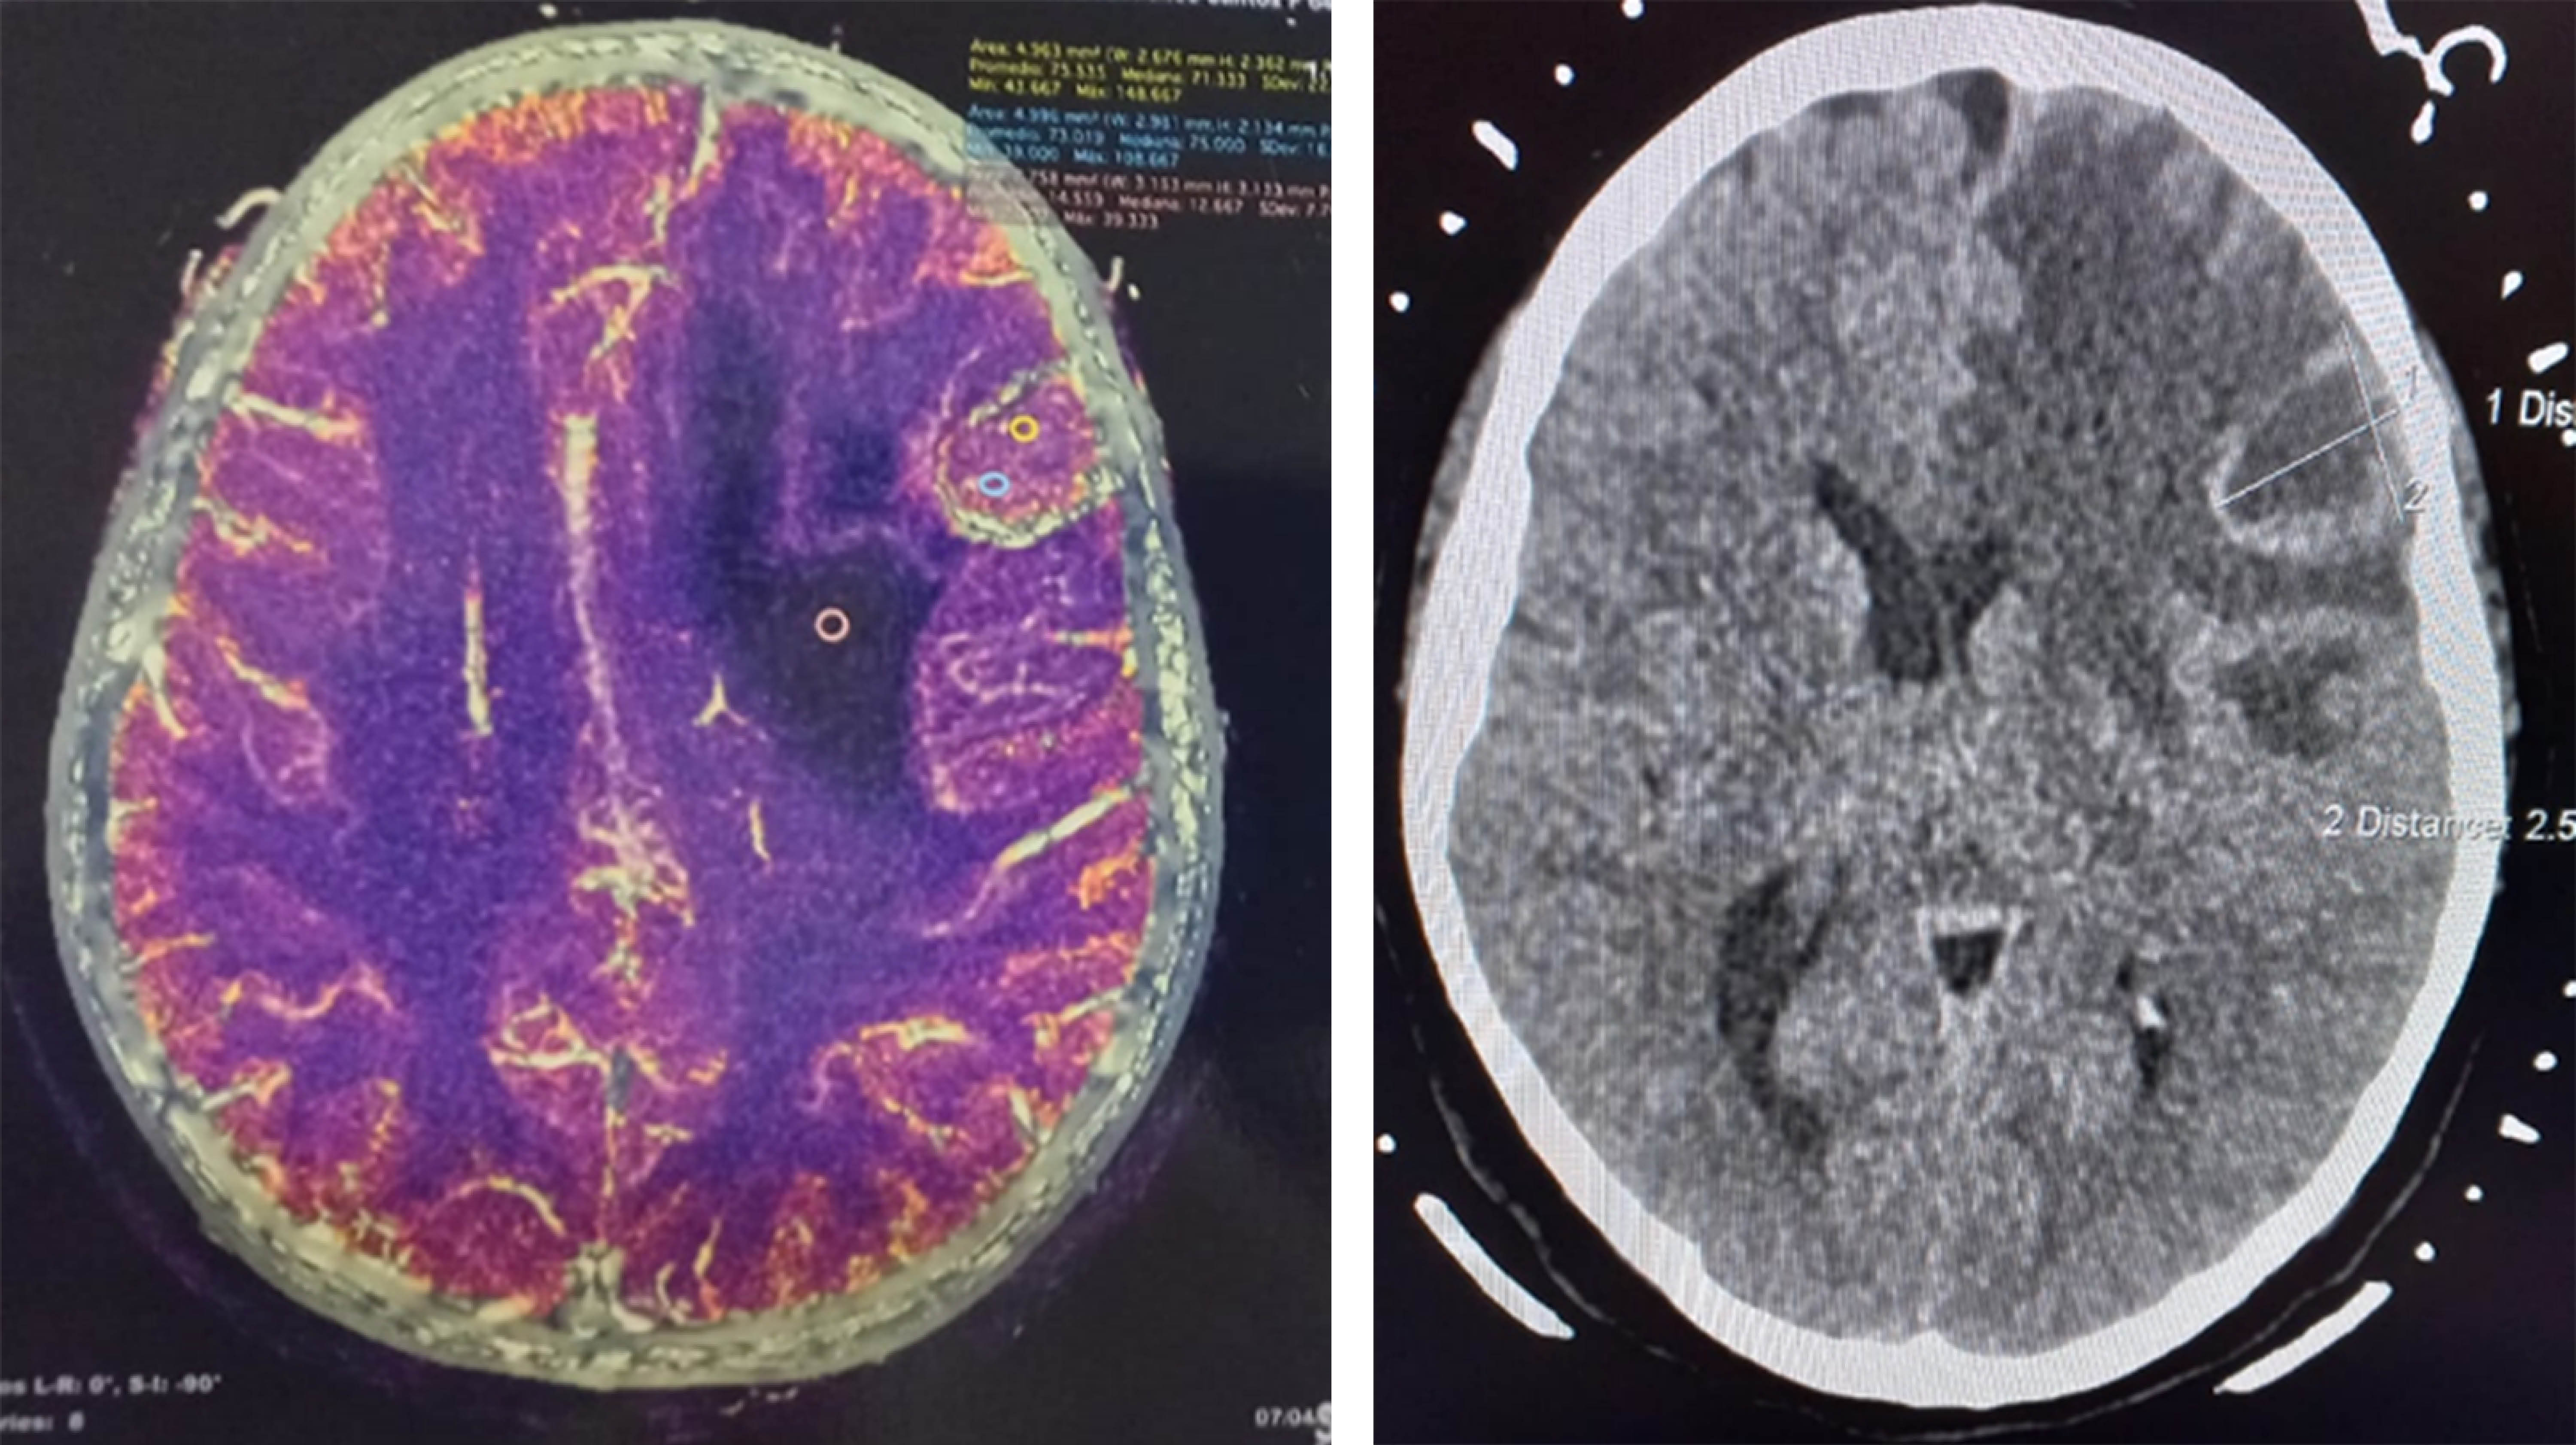

Paciente femenino de 64 años con diagnóstico de lesión tumoral frontoparietal derecha, con antecedente de cáncer colorrectal en remisión. Plan quirúrgico: craneotomía para resección tumoral (Figura 1). Técnica anestésica: inicialmente bajo anestesia total endovenosa con perfusión de dexmedetomidina, remifentanilo y propofol; vía aérea asegurada con mascarilla laríngea Supreme 4. Se realiza bloqueo de escalpe de seis zonas, bilateral, con ropivacaína al 0.5% y se coloca fijador craneal. Tras la craneotomía, se disecan meninges e inicia la emersión de anestesia general para realizar la resección tumoral. Se mantiene paciente bajo sedación consciente con anestesia total intravenosa (TIVA, por sus siglas en inglés) (remifentanilo y dexmedetomidina); se realizan pruebas neuropsicológicas durante la resección tumoral, sin alteraciones. Se termina el procedimiento quirúrgico y la paciente egresa a hospitalización para vigilancia. Tras una evolución y controles de imagen favorables, la paciente es egresada a domicilio sin alteraciones neurológicas.

Figura 1